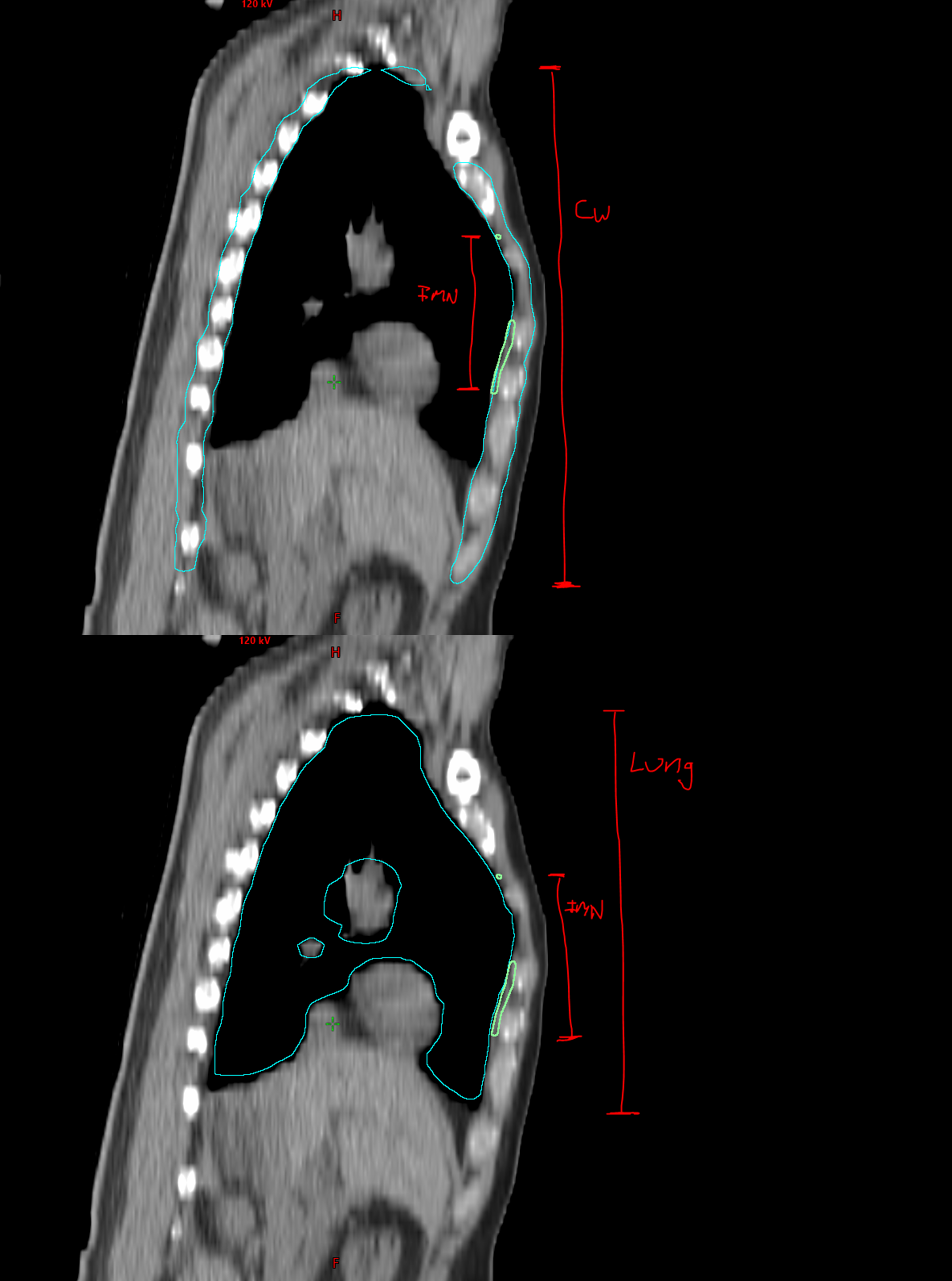

- Introduced normalized ratio metrics (IMN:Lung, IMN:Chest Wall) to reduce anatomical variability bias.

- Implemented relative ratio metrics between the IMN and reference organs to enhance filter reliability and account for anatomical variability across patients.

One of the main challenges was that filtering contours based purely on their absolute length along the z-axis could inadvertently exclude patients with atypical anatomy, such as very tall or very short individuals. To address this, we instead used ratios (such as IMN:Lung and IMN:Chest Wall) to normalize contour dimensions relative to each patient’s anatomy.

Clinical contours were too inconsistent to serve as a reliable ground-truth. The reviewed subset of Limbus contours was more effective for QA. The most common failure mode was incorrect Z-dimension contouring. Absolute length metrics introduced patient-size bias, making normalized ratios a better approach.